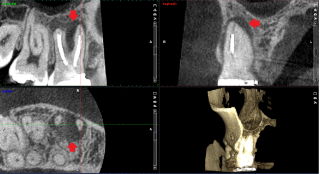

それでは、実際のCTスキャン画像をみながら説明いたします。以下は、根管治療時のCTスキャン画像です。左のレントゲン画像の歯のCT画像が右にあります。レントゲン画像では確認できなかった根尖病巣の黒い影(赤い矢印の先の影)が、いずれもはっきり確認できます。

下のCT画像では、根管治療で見落とされているらしい根管(赤い矢印のところ)が確認できます。白い線状のものは根管の蓋、赤い矢印の先の黒い線状のものは根管に蓋がされていない状態です。根尖病巣(歯根をとり囲む影)の原因は、赤い矢印のところの未治療の根管の細菌感染が原因と思われます。